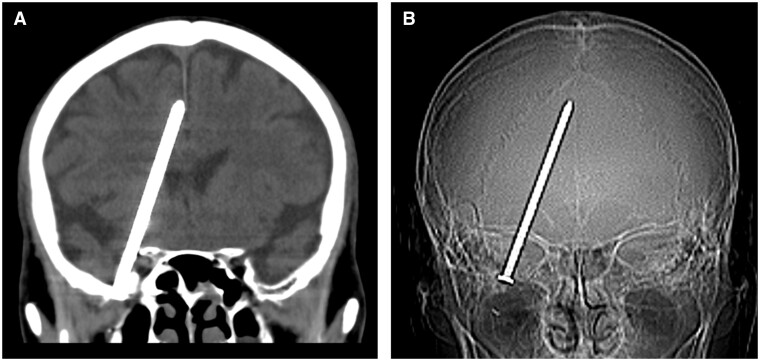

本病例报告深入探讨了一起独特的核磁共振成像诱发头痛的病例,其病因是一个未被发现的颅内异物。一名男性患者出现持续性头痛,进入核磁共振成像室后疼痛加剧,阻碍了成像过程。随后的头部 CT 扫描显示,颅腔内有一枚钉子,源于之前的射钉枪伤害。手术取出被认为不安全,因此需要继续观察。该病例强调了在核磁共振成像室中谨慎探查异常症状的必要性,敦促医护人员考虑潜在的异物。该事件强调了金属碎片在核磁共振成像过程中引起并发症的风险,并突出了在进行核磁共振成像之前对患者进行全面评估的重要性。

This case report delves into a unique occurrence of MRI-induced headaches attributed to an unsuspected intracranial foreign body. A male patient, presenting persistent headaches, experienced exacerbation of pain upon entering the MRI suite, hindering the imaging procedure. A subsequent head CT scan revealed a nail within the cranial cavity, stemming from a previous nail gun injury. Surgical removal was deemed unsafe, leading to continued observation. This case emphasizes the need for cautious exploration of abnormal symptoms in the MRI suite, urging healthcare professionals to consider potential foreign bodies. The incident underscores the risk of metallic fragments causing complications during MRI procedures and highlights the importance of thorough patient assessment before resorting to MRI imaging.